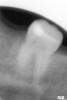

Лара3 Опубликовано 12 сентября, 2013 Автор Поделиться Опубликовано 12 сентября, 2013 (изменено) Прилегание той пломбы, что на снимке видно- плохое, есть патологический процесс под ней, да и на контактной поверхности скрытый кариес. По мне, так -это 'мартышкин труд'это скорее всего помеха рентгена, вот еще 1 снимок - там все в норме. к тому же к этой пломбе нет претензий и не было. Изменено 12 сентября, 2013 пользователем Лара3 Ссылка на комментарий

juli63 Опубликовано 12 сентября, 2013 Поделиться Опубликовано 12 сентября, 2013 Кариес скрытый у вас там. Снимок плохого качества. Ссылка на комментарий